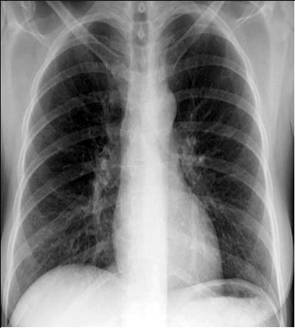

照片名称:高血压心脏病